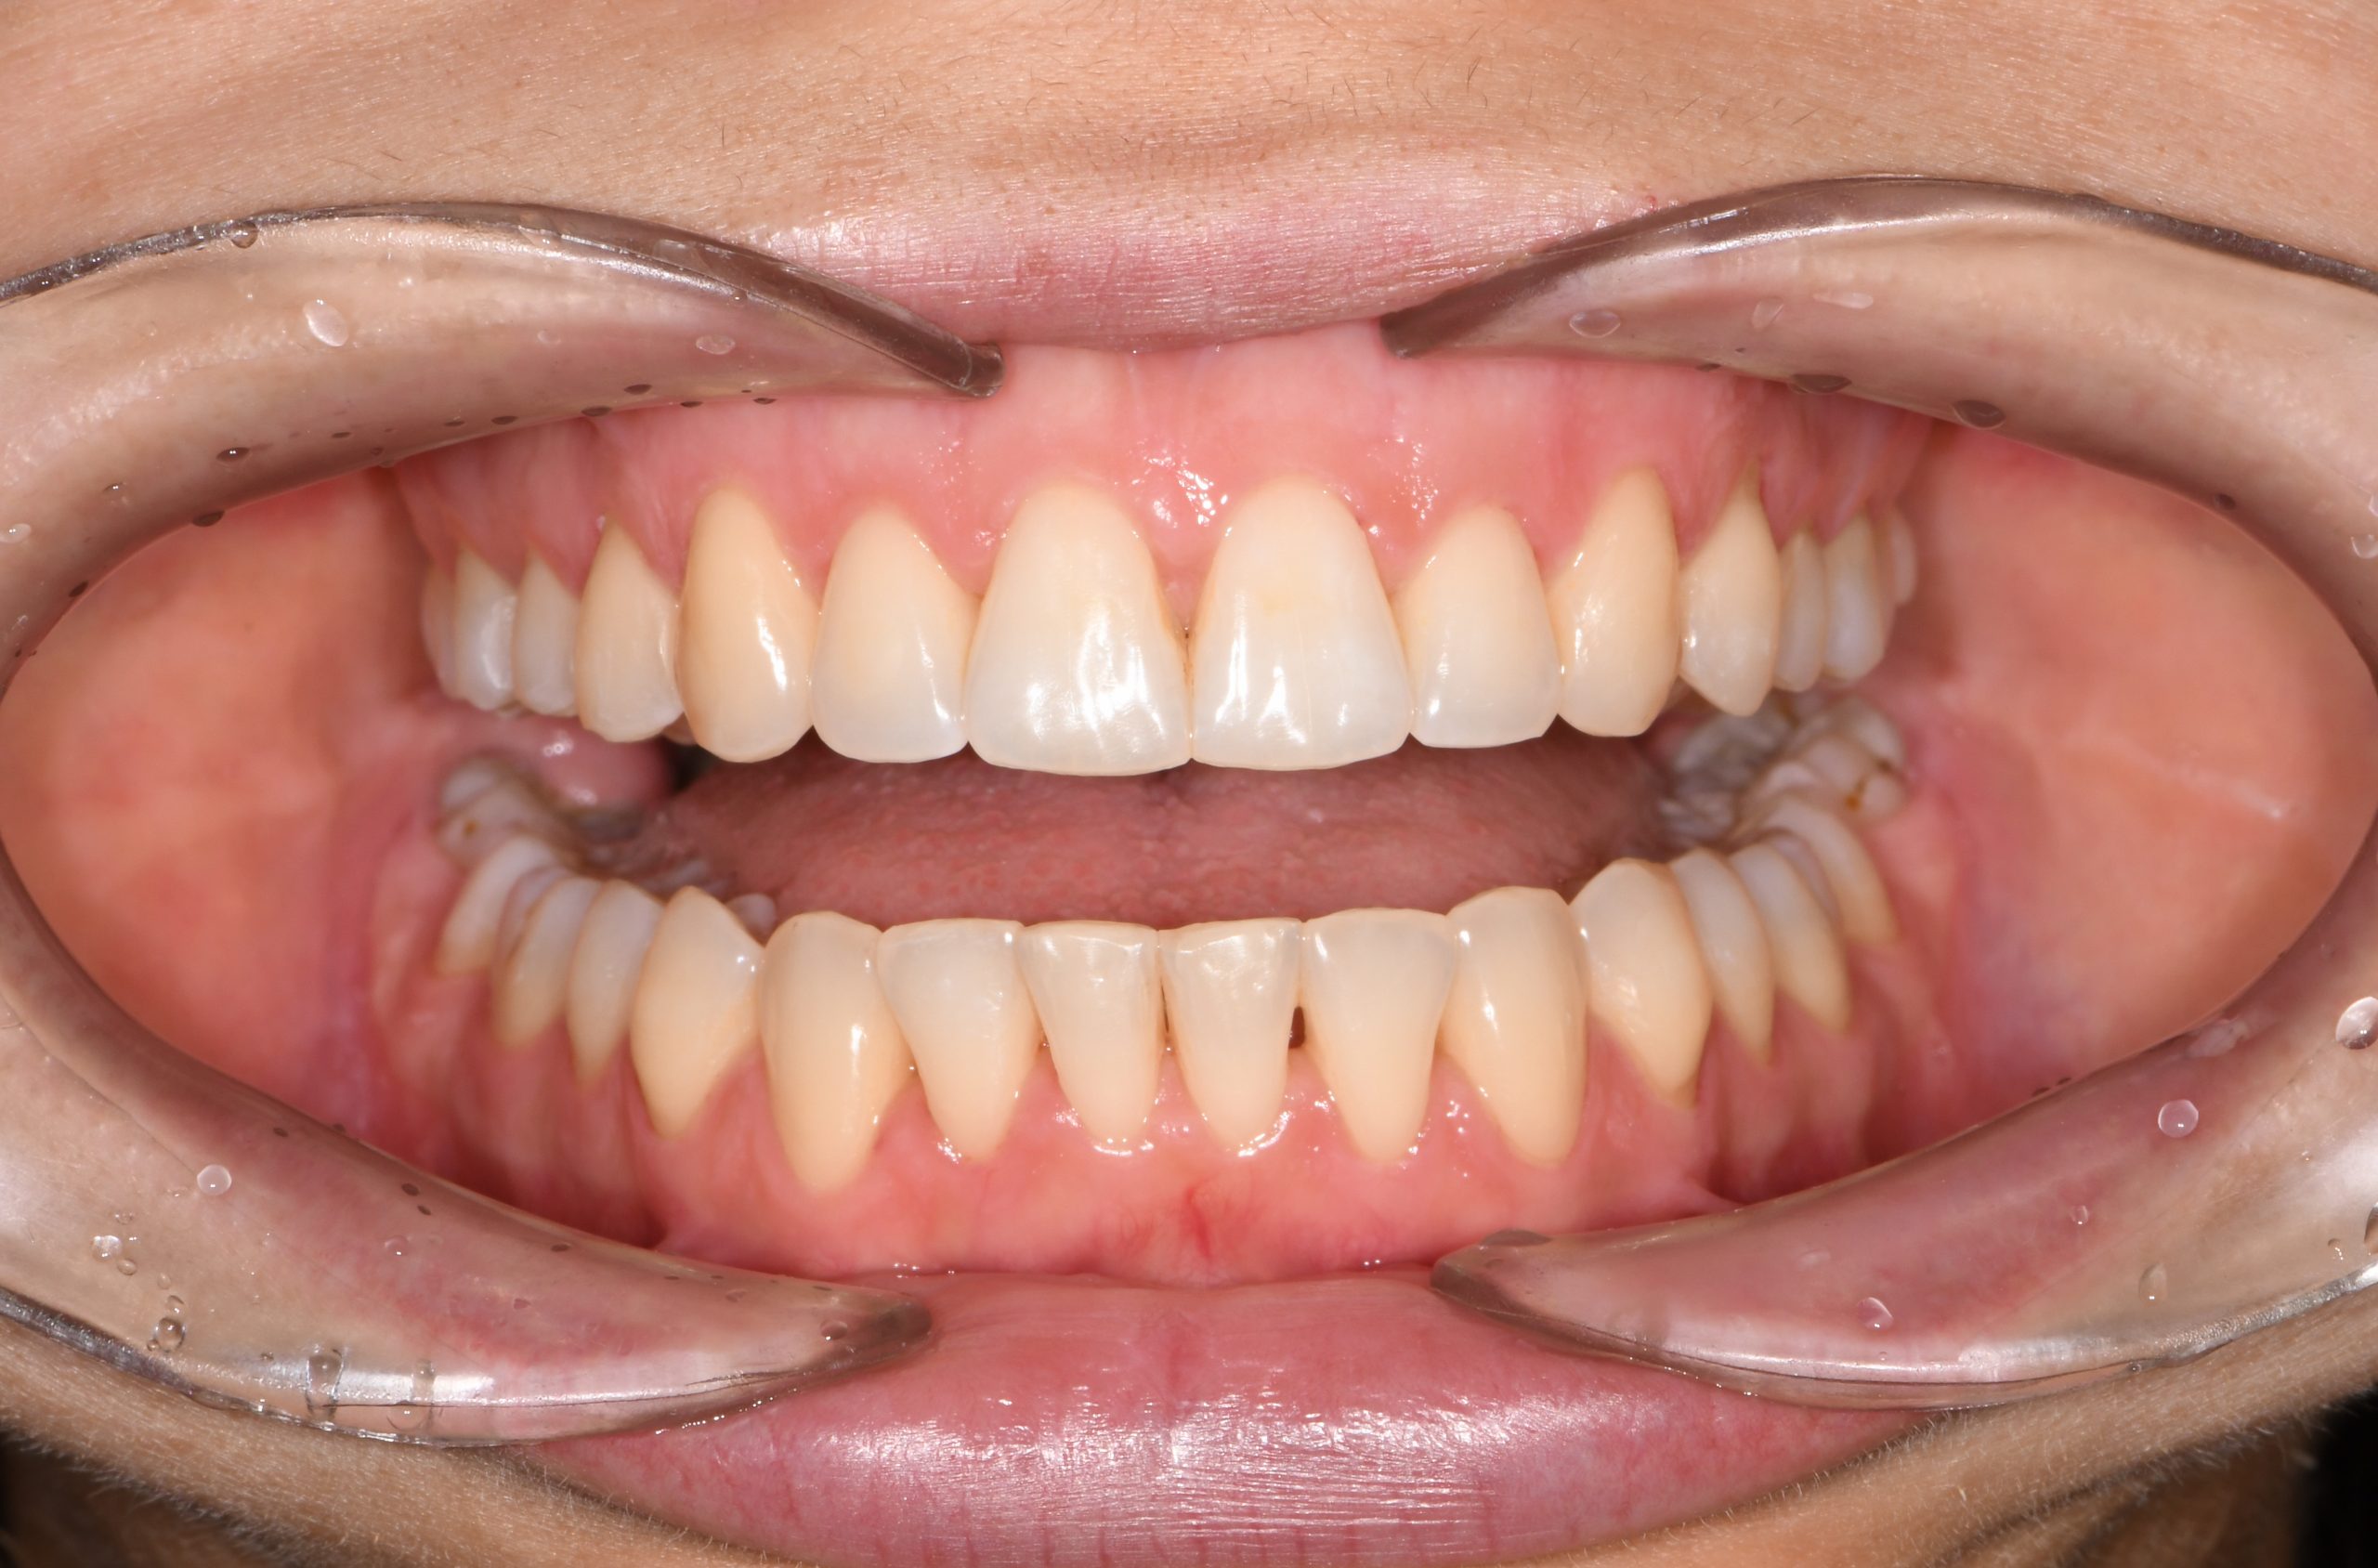

Az elmúlt évekből rengeteg szakmai referenciát tudnánk bemutatni, amelyek különböző fogszabályozási problémákat oldottak meg. Válogatva a több száz esetből, ezen az oldalon olyan képeket, információkat igyekeztünk bemutatni, amelyeknek a segítségével a jövőbeni pácienseinknek azt tudjuk üzenni: A Te fogsorod is lehet gyönyörű!

(Képeket a Pácienseink külön írásos beleegyezésével mutatjuk be!)